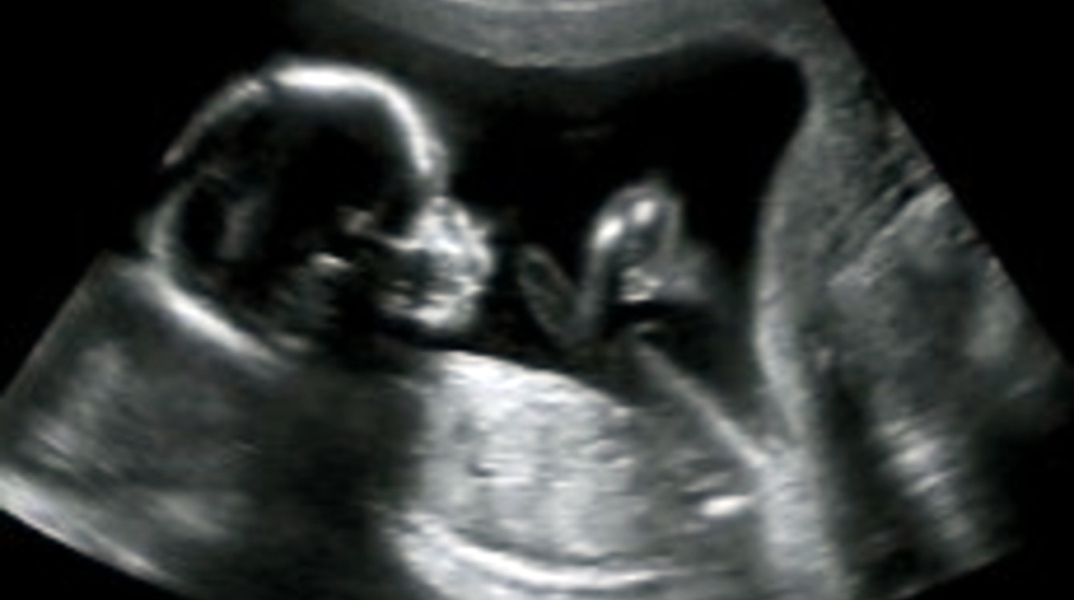

Η Άιοβα απαγορεύει τις αμβλώσεις στο πρώτο χτύπημα της καρδιάς του εμβρύου

Την πιο αυστηρή νομοθεσία για τις αμβλώσεις υιοθέτησε η πολιτεία της Άιοβα, βάσει της οποίας απαγορεύεται ο τερματισμός μιας κύησης από τη στιγμή που μπορεί να εντοπιστεί ο καρδιακός παλμός του εμβρύου.

Μόλις τεθεί σε εφαρμογή θα απαγορεύονται οι αμβλώσεις μετά την έκτη εβδομάδα της κύησης με εξαίρεση τις περιπτώσεις βιασμού ή αιμομιξίας.

Βάσει του λεγόμενου νομοσχεδίου «του καρδιακού παλμού» όποια γυναίκα επιθυμεί να κάνει έκτρωση θα πρέπει να υποβάλλεται σε υπερηχογράφημα. Στην περίπτωση που εντοπιστεί καρδιακός παλμός στο έμβρυο, δεν θα της επιτρέπεται. Οι εξαιρέσεις αφορούν τους βιασμούς ή τις περιπτώσεις αιμομιξίας, οι οποίες έχουν καταγγελθεί στις αρχές, ή όταν βρίσκεται σε κίνδυνο η ζωή της γυναίκας.